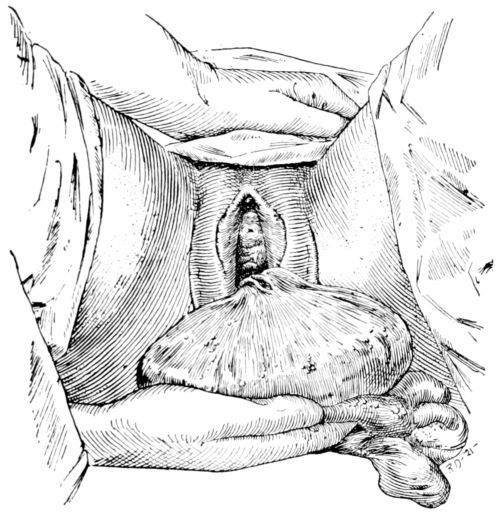

| 85. | Baby’s head appearing at vulva | 266 |

| 155. | Preparation for circumcision | 468 |

| 156. | Baby draped with sterile sheet, in above | 469 |